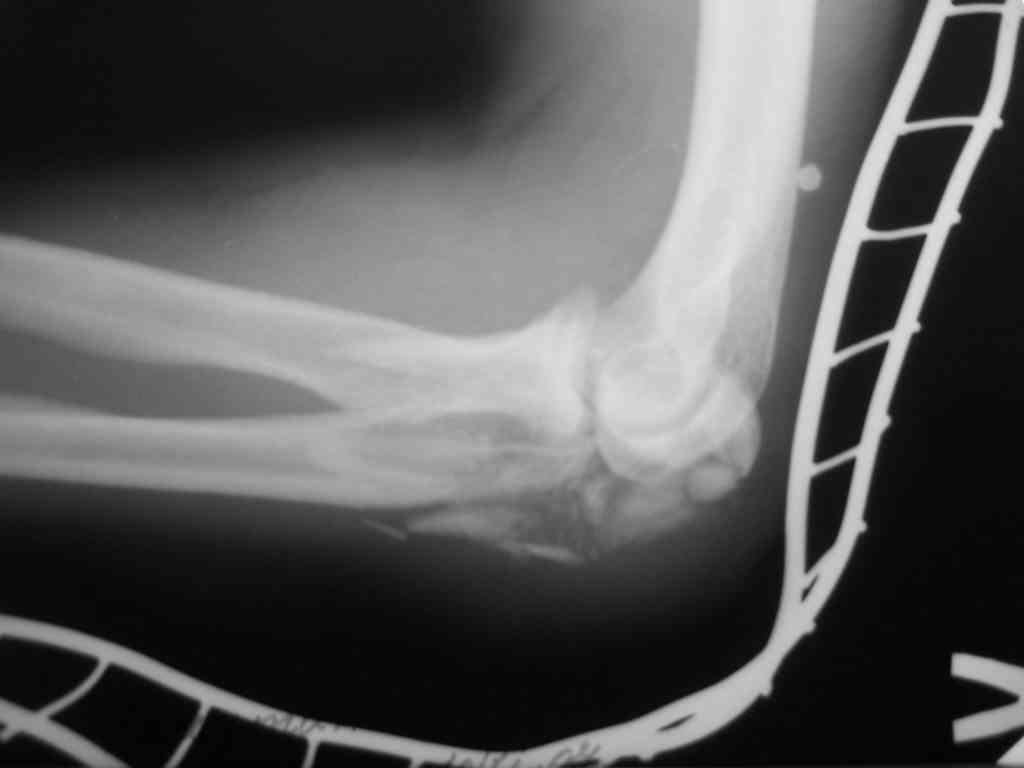

Поступил больной с Диагнозом:Закрытый оскольчатый  перелом локтевого

отростка слева.

С таким перелом встретились в первый раз.

У какого есть опыт подскажите:

1.Хватит ли стандартного доступа (как при банальных переломах)

2.Выбор фиксатора?

3.Нюансы по ходу операции.

Спасибо за  внимание. (P.S извините за качество снимков)